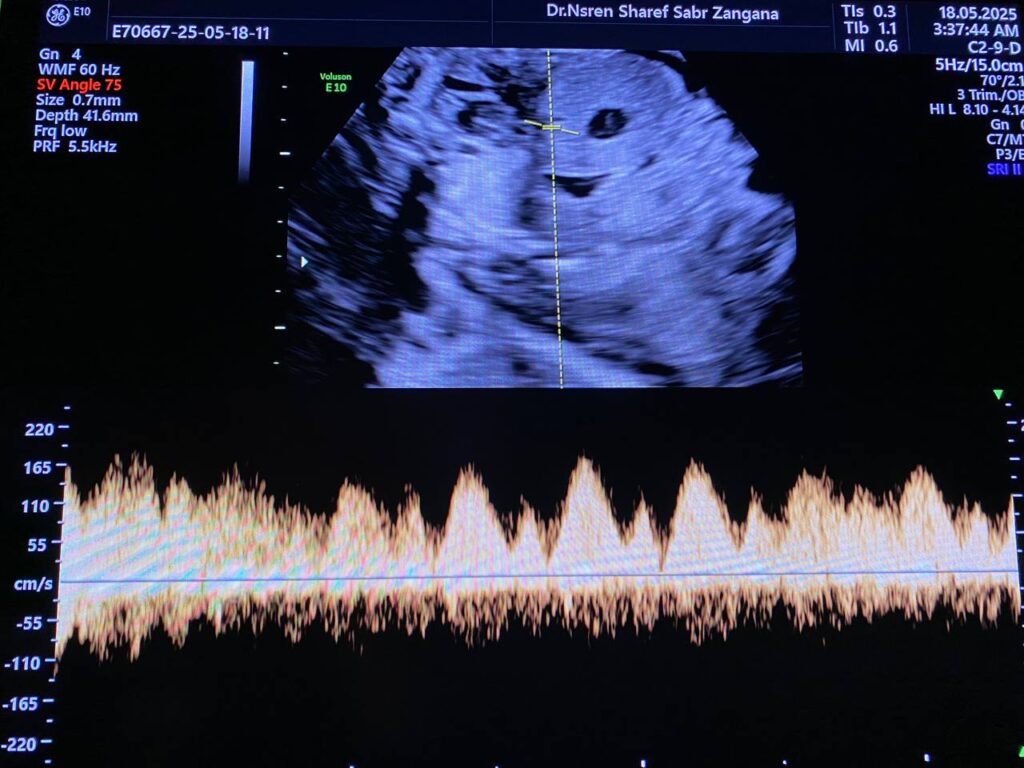

There’s focal Aneurysmal dilatation of the intrahepatic umbilical vein 10mm, normal ductus venosus flow seen, Also presence of small Blakes pouch cyst 4x5mm

At 29wk pregnancy